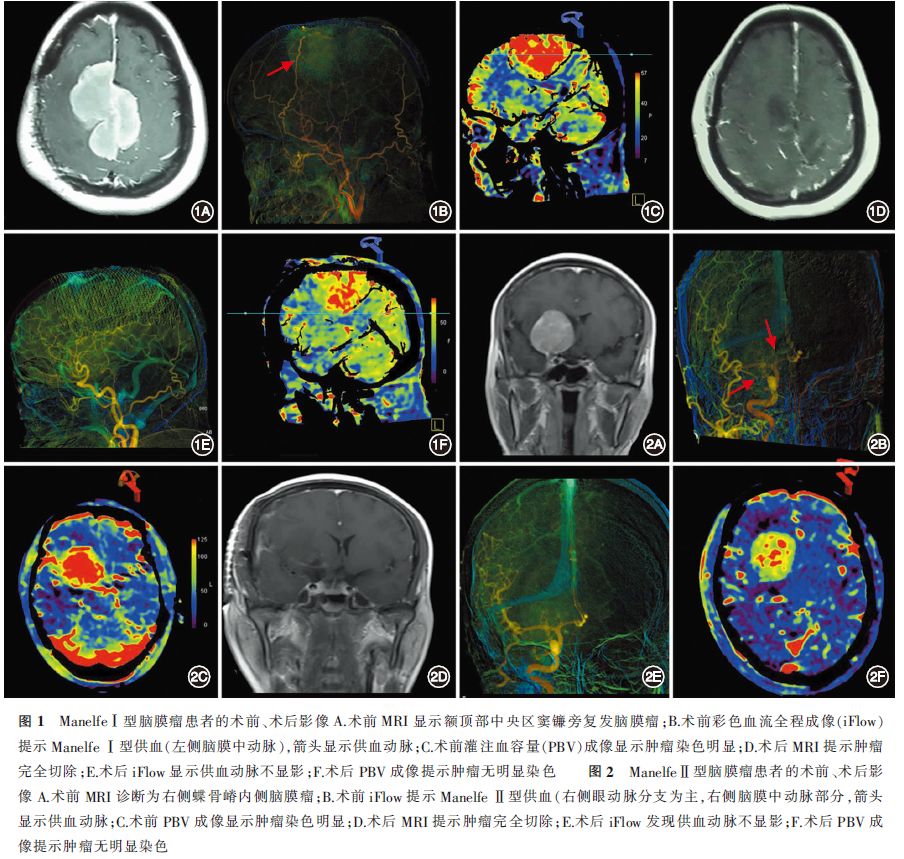

1. 栓塞情况:根据Manelfe供血分型,Ⅰ型7例, Ⅱ型10例, Ⅲ型4例。17例Manelfe Ⅰ型(图1)和Ⅱ型(图2)者均行血管内栓塞,栓塞完成后肿瘤供血动脉不显影,肿瘤无明显染色。4例 Manelfe Ⅲ型未栓塞。均未发生与栓塞相关的严重并发症。

2. 肿瘤切除情况:术后MRI提示所有肿瘤均达到全切除(Simpson分级Ⅰ级),病理均证实为脑膜瘤,未出现严重的术后并发症。